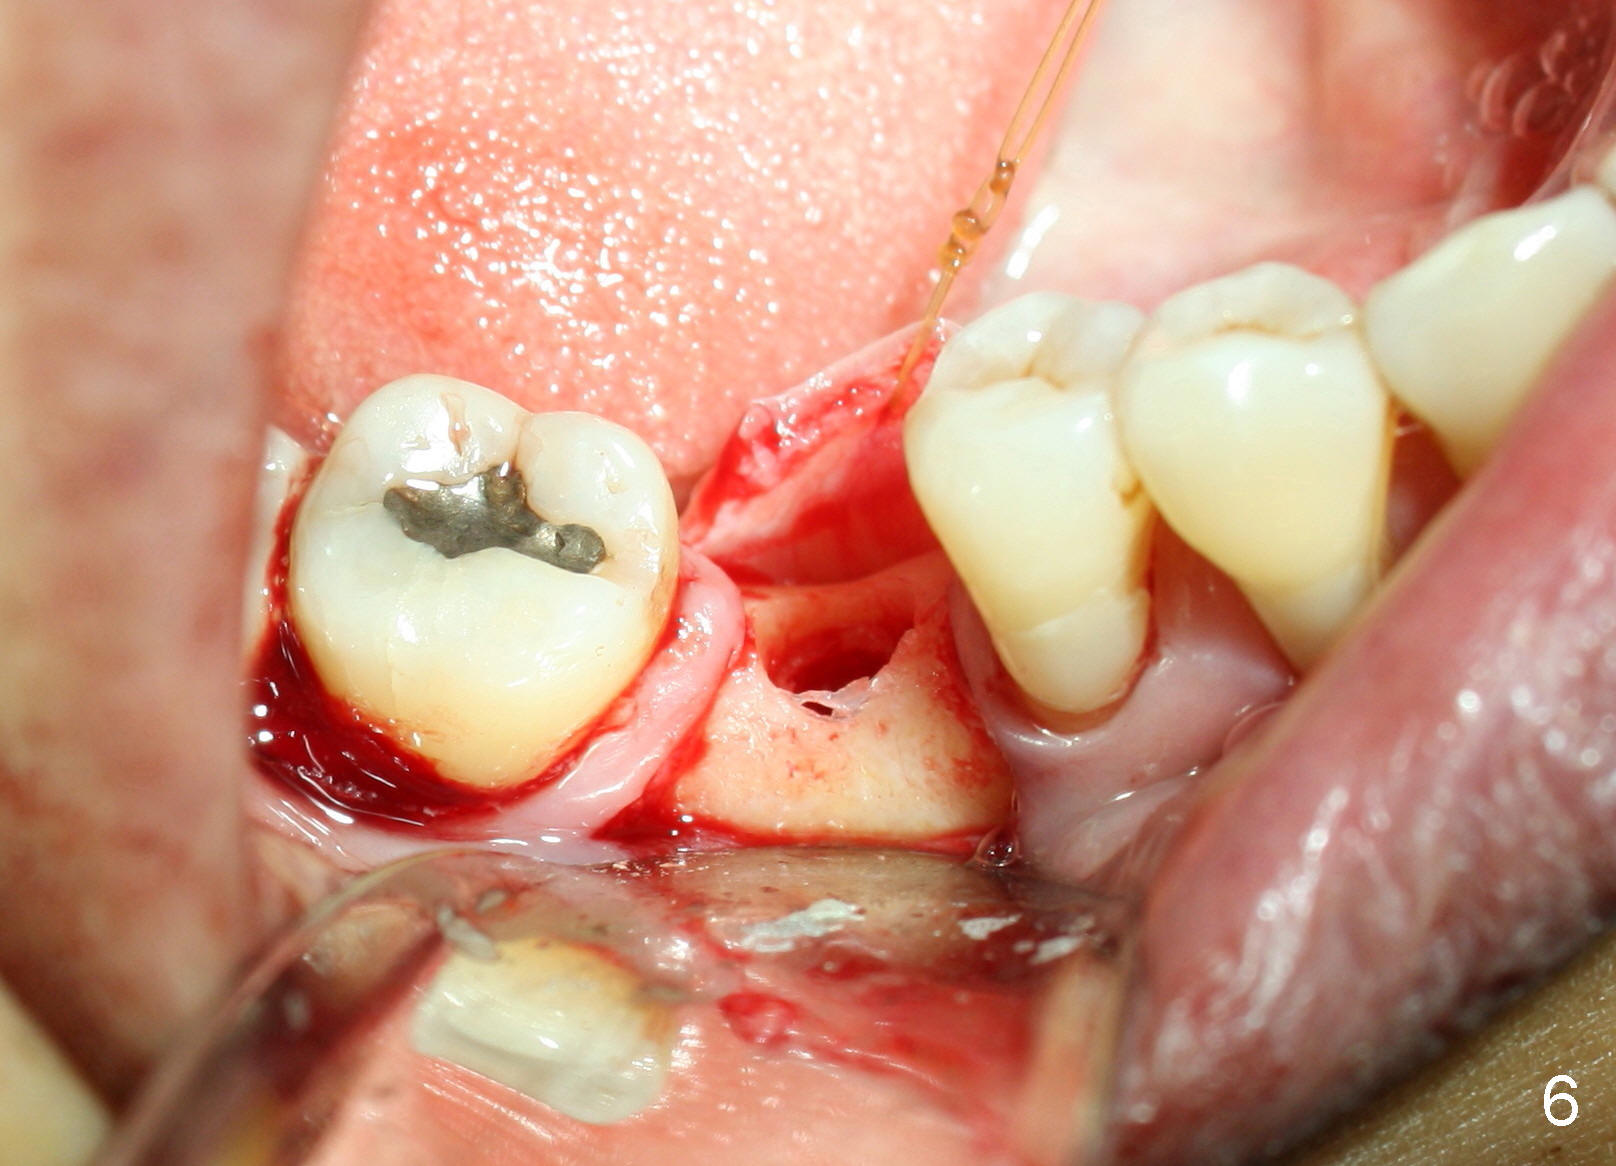

Due to unavailability of bone-level implant, a tissue-level implant is to be placed as a backup (Fig.1: 4.5x17 mm). Osteotomy is initiated with 1.5 mm pilot drill at depth of ~ 10 mm; the trajectory appears to be as good as expected (Fig.2). Osteotomy is gradually increased to 4.5x17 mm, followed by insertion of 4.5x17 mm tap (Fig.3,4). The ostetomy appears to be deviated lingual (Fig.5). When the tap is removed, the buccal plate appears to be thin (Fig.6). A tapered implant is placed (Fig.7).